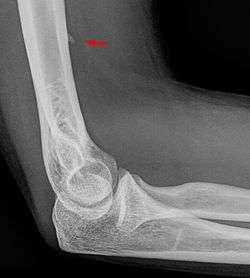

![]() Small supracondylar process seen on a lateral radiograph of the elbow | |

The supracondylar process of the humerus is a bony projection on the anteromedial aspect of the upper arm bone (humerus), about 5 cm above the medial epicondyle. It is directed downward, forward and medially pointing to the medial epicondyle. It is an anatomical variation which occurs in about one percent of all people. A fibrous band, Struthers ligament, may connect this process to the medial epicondyle.